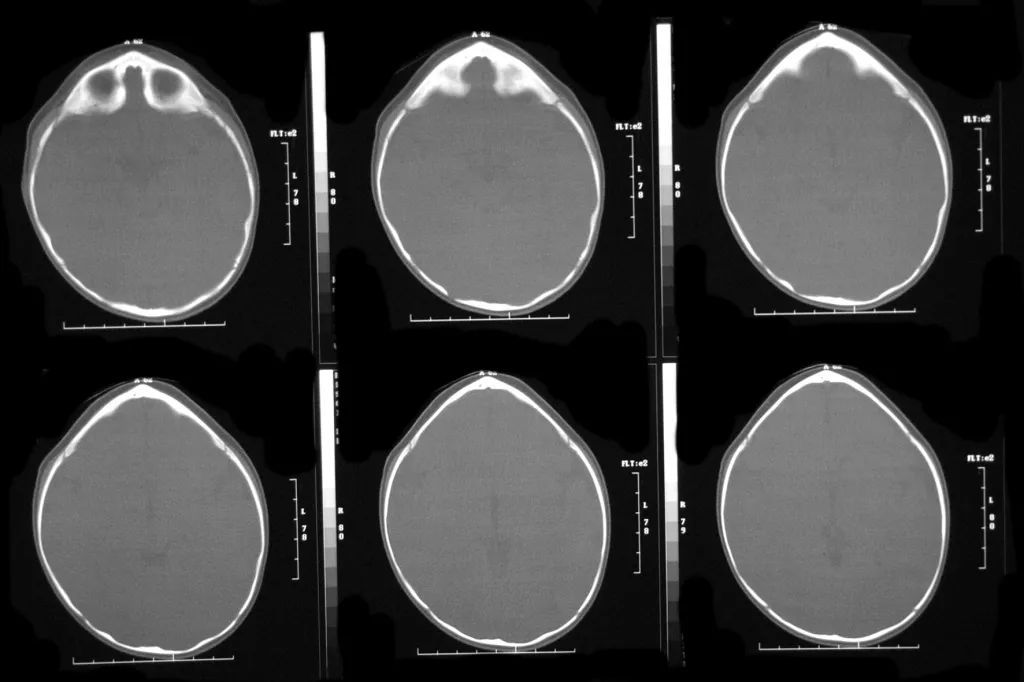

At El Paso Craniofacial Team, the primary treatment for craniosynostosis is surgery. First performed in the late 1800s, surgical approaches have continued to evolve and improve. The two main approaches are Calvarial Vault Remodel (CVR) and endoscopic-assisted surgery, with each tailored to the child’s age, the affected suture, and the severity of the condition.